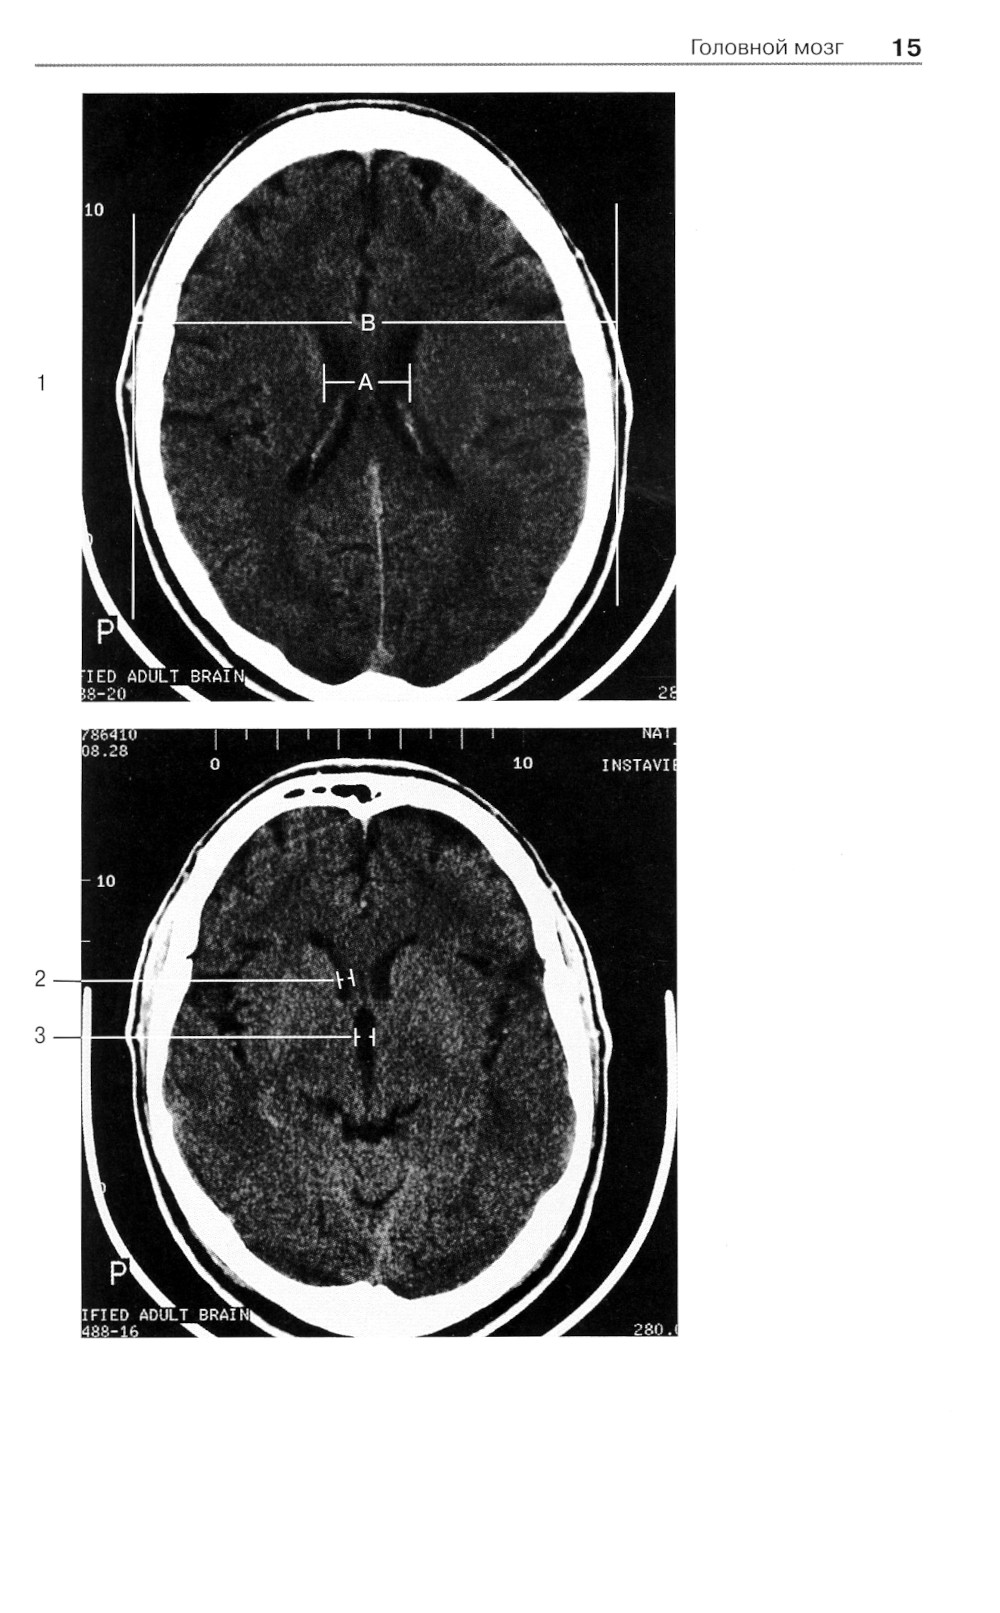

Аннотация: Норма при КТ- и МРТ-исследованиях. 6-е изд

Широкое использование в современной клинической практике компьютерной томографии и магнитно-резонансной томографии как решающих методов диагностики при многих болезнях, относящихся к различным клиническим специальностям и разным анатомическим областям, выдвигает на первый план проблему границ между нормой и патологией при трактовке «изображения на срезах». Помочь врачу - специалисту, составляющему заключение на основании анализа изображений, полученных при КТ- и МРТ-исследованиях, - основная задача этой книги, которая как бы продолжает ранее вышедшую книгу «Норма при рентгенологических исследованиях». Каждому из названных методов посвящен самостоятельный ее раздел, охватывающий все исследуемые анатомические области (голова и шея, грудная клетка и т.д.).| Издательство | МЕДпресс-информ |